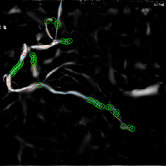

Refer to caption

(a) (a1)

(b) (a2)

(c) (a3)

(d) (b1)

(e) (b2)

(f) (b3)

Figure 9: Comparison of the interactive stenosis detection before ((a)) and after ((b)) the introduction of the potential energy function

The comparison of the detection results before and after the algorithm improvement, i.e., the introduction of the potential energy function, are shown in Fig. 9. By comparison, we can see that the improved algorithm has good robustness for arc structure, bifurcation structure, and even ring structure with large curvature.